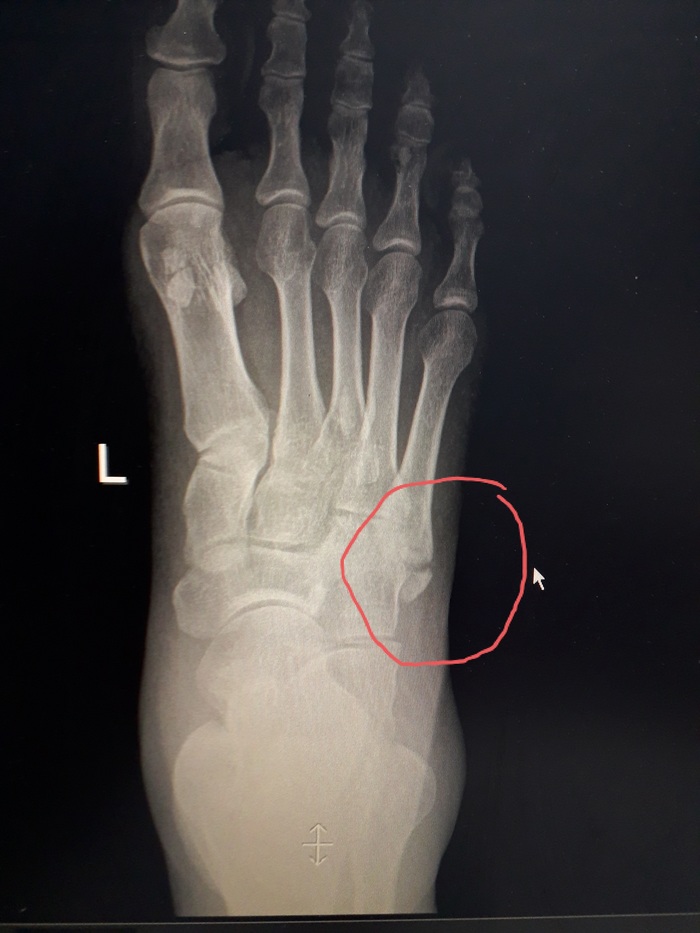

Вобщем почти 2 недели назад сломал ногу. Подвернул и сломал 5ю плюсневую.

Я потопал. Сделал рентген( на фото рентген не из этой травмы, там я не смог сфоткать). Потом пришел обратно. Этот дядя потыкал ручкой в экран где то в этом районе( на фотке)

- Видишь, вот он твой перелом?

Вчера поехал. Там травматолог- женщина посмотрела и отправила на снимок ибо говорит что то странное. Эти снимки я конечно сфотал. На них она мне и показала реальный перелом. Кто не догадался - вот он.

Как вы понимаете это совершенно другое место. У основания.

Вобщем гипс мне наложили совсем не тот что нужно и не там где нужно.

Почти две недели псу под хвост. Ибо ничего не сросталось, потому что ступня двигалась. И отек потому и не спадал.